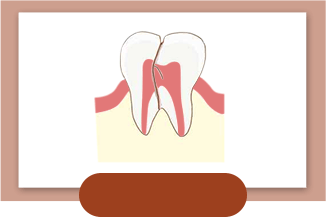

牙齿隐裂

-